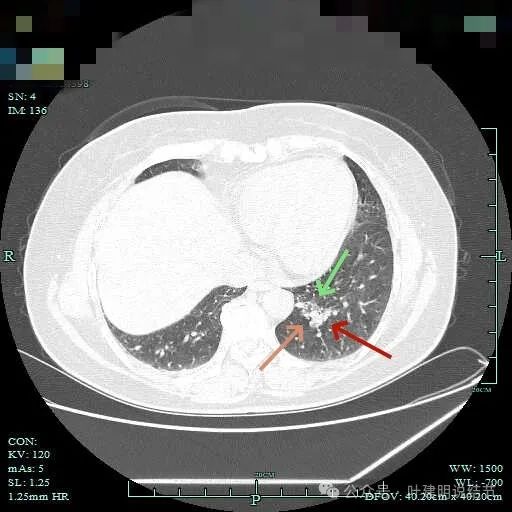

灶内细支气管扩张明显,实性成分缺乏收缩力,考虑腺泡亚型。

磨玻璃成分也很明显,考虑含贴壁亚型。